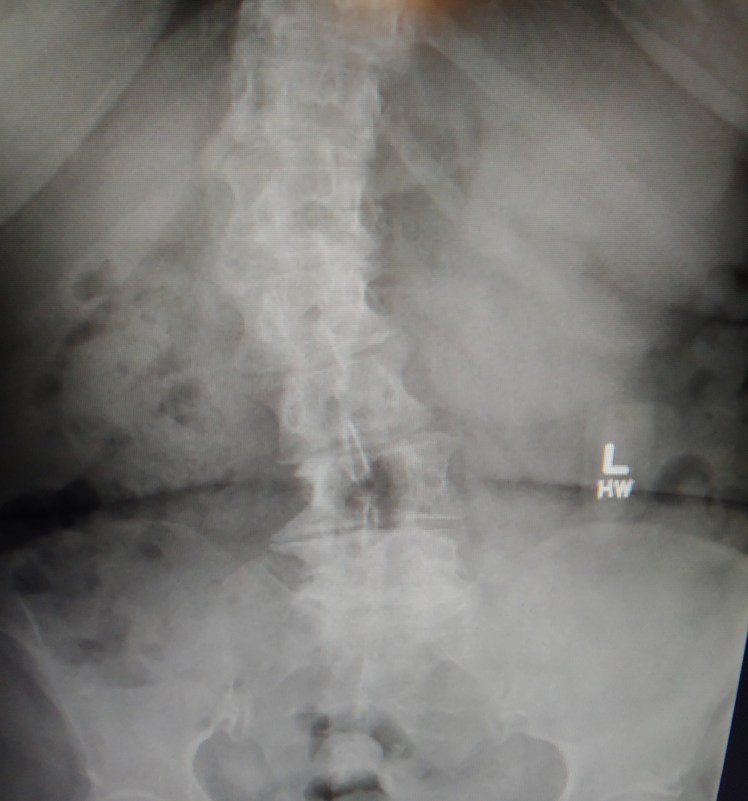

The bone makes a spur by overgrowing the parts of the vertebrae rubbing against each other. Spurs are the body’s response to inflammation or osteoarthritis. Here is an x-ray of moderate lumbar (lower back) scoliosis. See the spurs on the lower right vertebrae?

When those rubbery cushions get thinner from wear and tear, different things can happen. In my case I had what’s called bone spurs to form, because I have scoliosis which has worsened over the last 9 years.

Scoliosis is a side to side curving, of the spine which makes some of the vertebrae get out of alignment, which can eventually cause the vertebrae to rub on each other and make bone spurs.